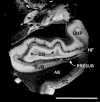

Ex vivo magnetic resonance imaging yields high resolution images that reveal detailed cerebral anatomy and explicit cytoarchitecture in the cerebral cortex, subcortical structures, and white matter in the human brain. Our data illustrate neuroanatomical correlates of limbic circuitry with high resolution images at high field. In this report, we have studied ex vivo medial temporal lobe samples in high resolution structural MRI and high resolution diffusion MRI. Structural and diffusion MRIs were registered to each other and to histological sections stained for myelin for validation of the perforant pathway. We demonstrate probability maps and fiber tracking from diffusion tensor data that allows the direct visualization of the perforant pathway. Although it is not possible to validate the DTI data with invasive measures, results described here provide an additional line of evidence of the perforant pathway trajectory in the human brain and that the perforant pathway may cross the hippocampal sulcus.